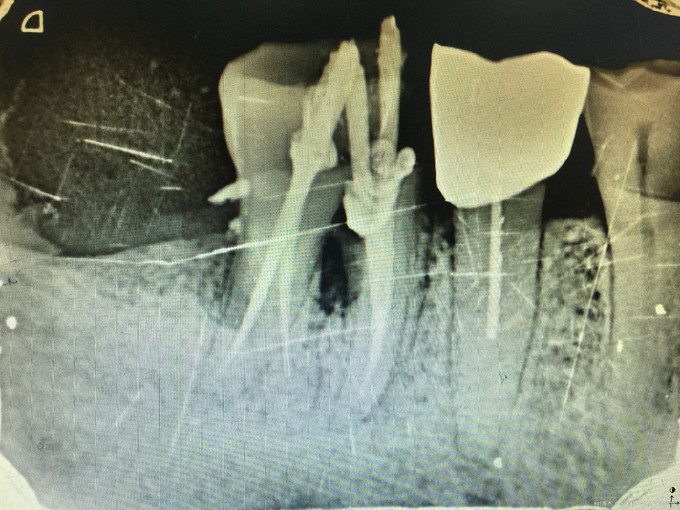

临床检查:46牙合面无明显龋坏,近中探疼(+),冷(++),叩(-),松动度(-),牙周正常. 辅助检查:X线示46近中邻面龋坏累积髓腔。

诊断:46牙髓炎 治疗:经患者知情同意后,46局麻去腐降牙合,开髓拔髓寻找根管口,建立直线通路,扩通根管,确定工作长度。S3/EDTA凝胶镍钛器械,低浓度次氯酸钠冲洗根管,预备至35/04,氢氧化钙诊间封药,一周后复诊,试主尖X线示恰充,试干根管,导AH-PLUS糊剂,VDW热压胶垂直加压根充,术后见根管恰充,暂封观察考虑冠修复。